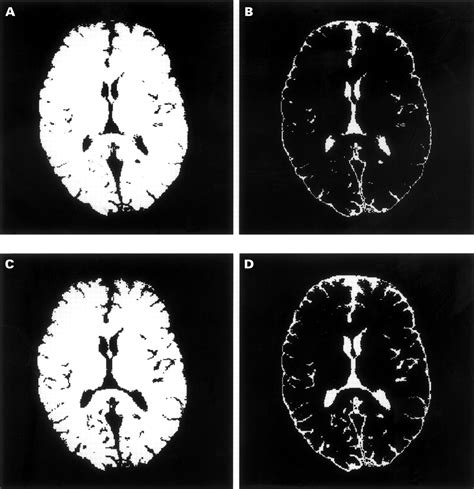

When a radiologist identifies volume loss, they usually assess the distribution of the atrophy. Generalized atrophy refers to widespread loss across the entire brain, while focal atrophy suggests that specific areas, such as the hippocampus or the frontal lobes, are being disproportionately affected. The following table provides a snapshot of how medical professionals categorize these findings:

Technological advancements in "volumetric MRI analysis" now allow doctors to quantify brain volume more precisely than in the past. These automated programs can compare a patient's brain size to normative databases, providing a more objective measure of whether the observed loss is truly abnormal for the patient's specific age and biological sex.